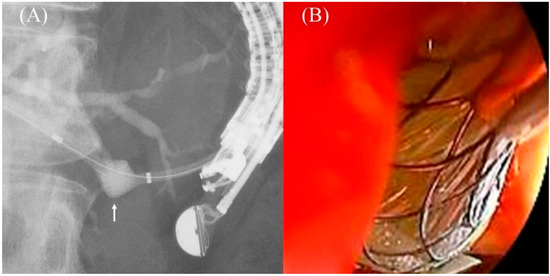

- Shima, Y.; Isayama, H.; Ito, Y.; Hamada, T.; Nakai, Y.; Tsujino, T.; Nakata, R.; Koike, K. Crisscross anchor-stents to prevent metal stent migration during endoscopic ultrasound-guided hepaticogastrostomy. Endoscopy 2014, 46 (Suppl. S1), E563. [Google Scholar] [CrossRef]

- Fujisawa, T.; Isayama, H.; Ishii, S. “ClipFlap” anchoring method for endoscopic ultrasonography-guided hepaticogastrostomy with a covered self-expandable metallic stent. Dig. Endosc. 2020, 32, 628. [Google Scholar] [CrossRef]